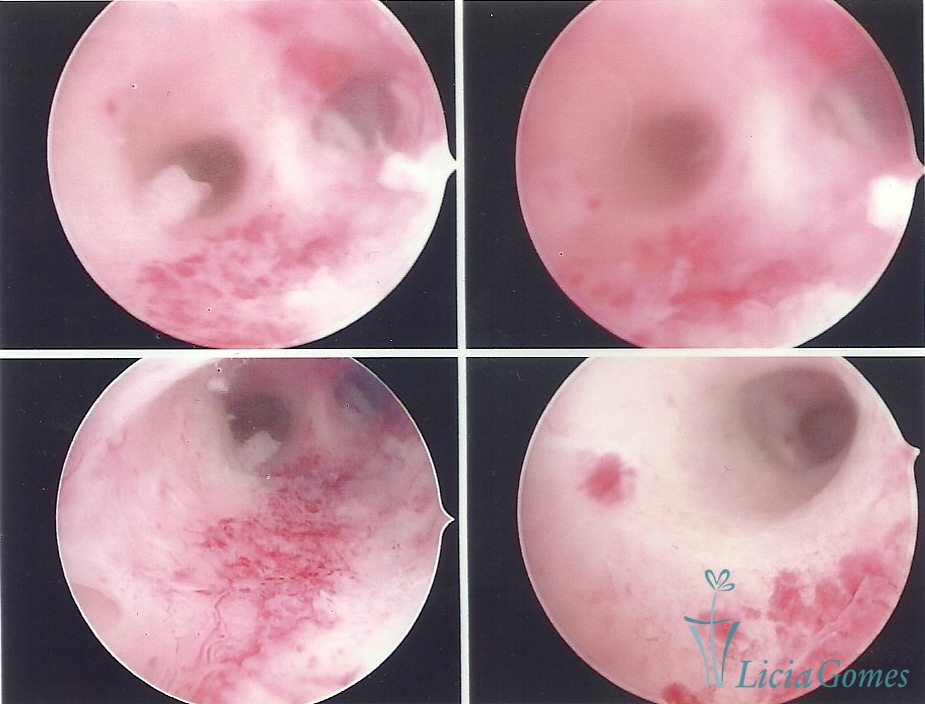

Uterus didelphys

The presence of two uterine cervices and a double vagina, similar to unicornuate uteri, with a normal covering of endometrium.